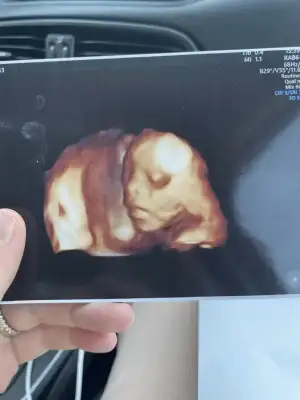

Saolun kızlar sizlerin yorumundan sonra rahatladım. Doktorla konuştum. Ayak şişmesi normal dedi. Yüz ve el şişerse detaylı anlamaya çalışırız dedi. Sizinde aklınızda olsun. Bizde bugün 18+5 teyiz ama daha kendisinden bir tepki alamadık :) ultrasonda el ensede yatıyordu. Keyifli yerinde herhalde :)

Çıktım canım, herşey yolunda şükür. 5 güm önden gidiyor. 500 gram 26 cm. Plesenta önde olduğu için geç hissetmişim. Çok zor gösterdi bebek yüzünü